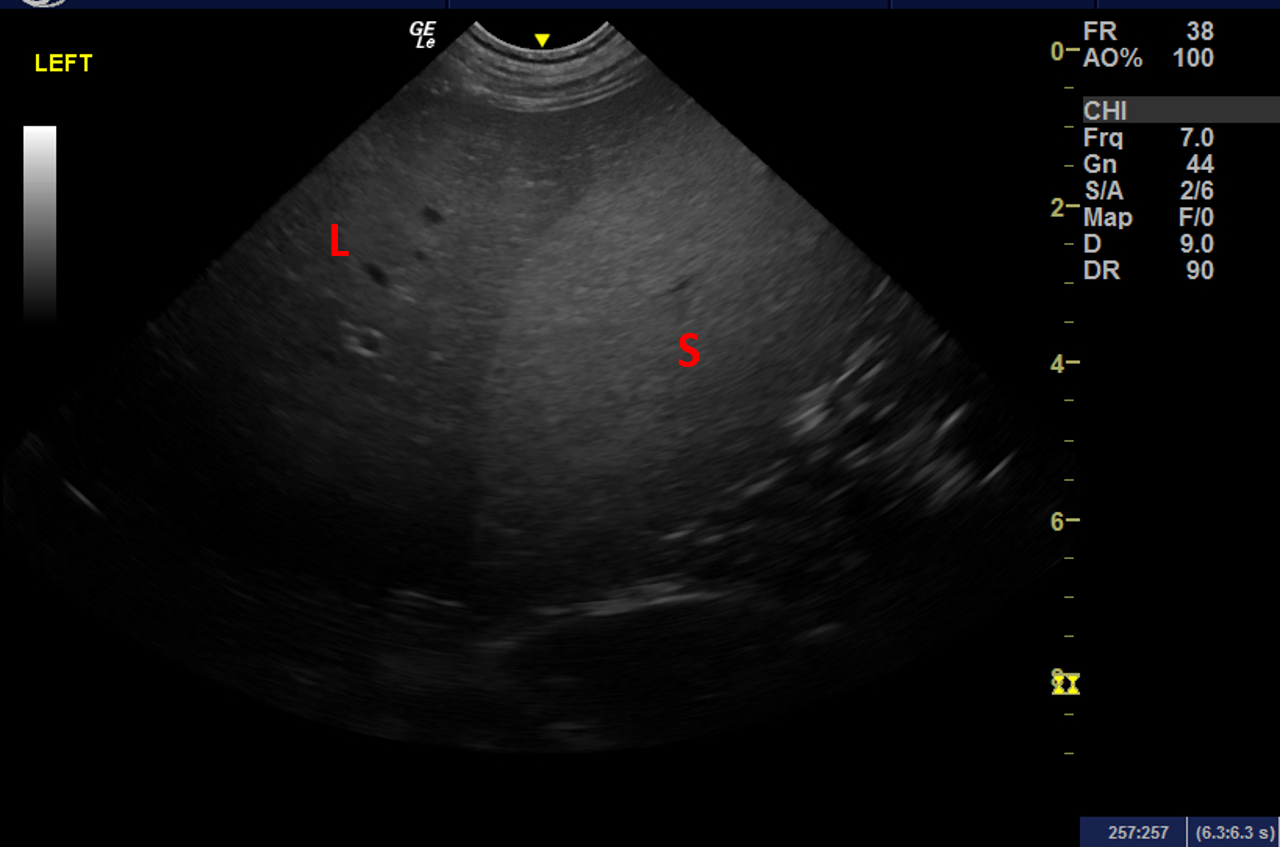

Ultrasonography of the Kidneys >>

Ultrasonography of the Spleen >>